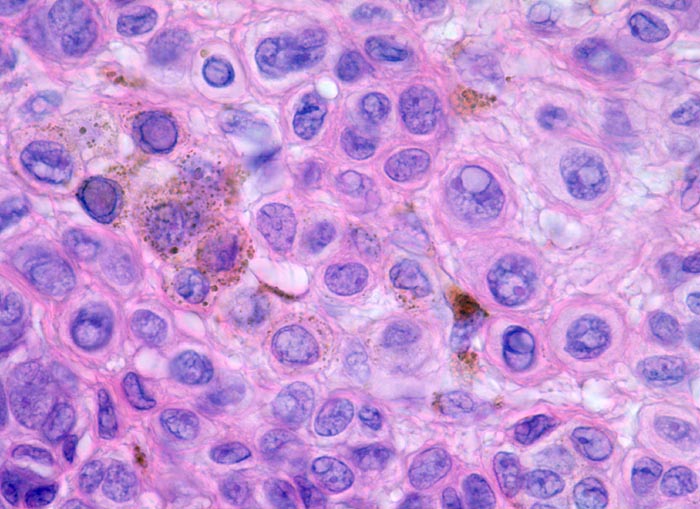

Oberflächliche Tumorzellen enthalten teilweise körniges braunes Melaninpigment.

Angrenzend an die pigmentierten Zellnester sind Melanophagen erkennbar, deren Zytplasma mit Melaningranula angefüllt sind.

Die oberflächlichen Naevuszellen zeigen reichlich helles, teils pigmentiertes Zytoplasma und helle ovale Kerne mit kleinen, deutlich erkennbaren Nukleolen. Zur Tiefe hin werden die Naevuszellen kleiner, haben weniger Zytoplasma und dunkle kleine Kerne ohne gut erkennbaren Nucleolus. Die Zellnester werden zur Tiefe hin ebenfalls kleiner (=Ausreifung).

Keine Mitosen, keine Zellatypien.